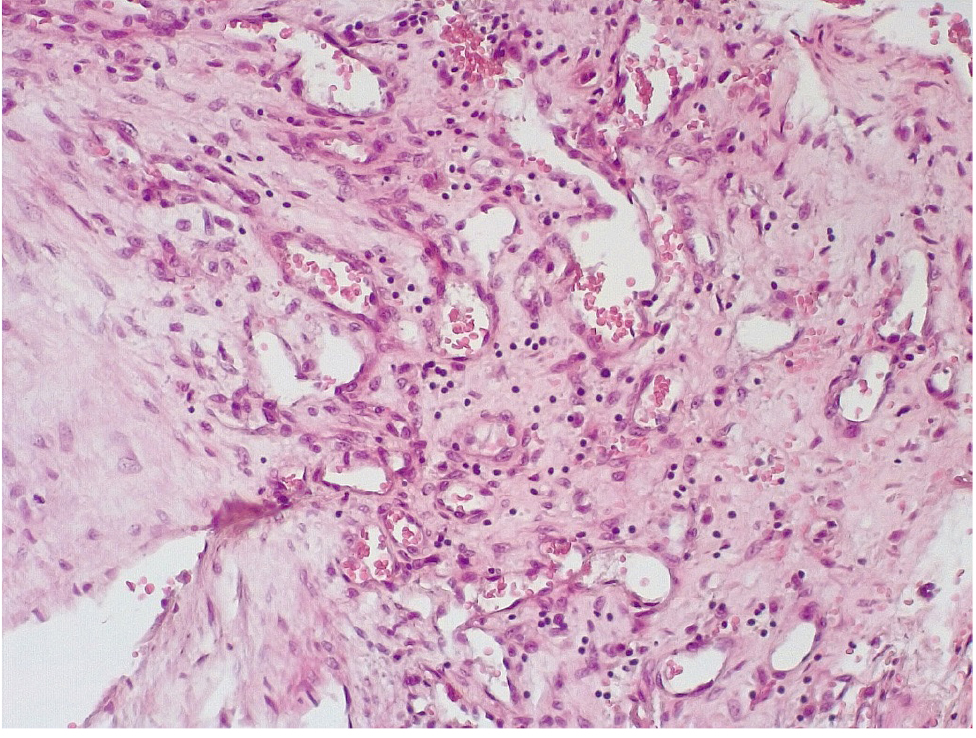

Патоморфологическое исследование стенок КА в ранние сроки после стентирования выявило характерные особенности. В течение первых 3 дней после стентирования в стенке КА имелась атерома с признаками геморрагий. Эндотелий был на большем протяжении разрушен, с признаками десквамации, с окружающей очаговой лейкоцитарной инфильтрацией. Вокруг атеромы, со стороны медии и адвентициальной оболочки, отмечалась умеренновыраженная лимфоцитарная инфильтрация (рис. 1).

Рис. 1. В стенке атеромы КА – геморрагии, умеренновыраженная лимфоцитарная инфильтрация медии и адвентиции. Десквамация эндотелия с очаговой лейкоцитарной инфильтрацией (1–3-и сутки). Окраска гематоксилином-эозином. Ув. ×100